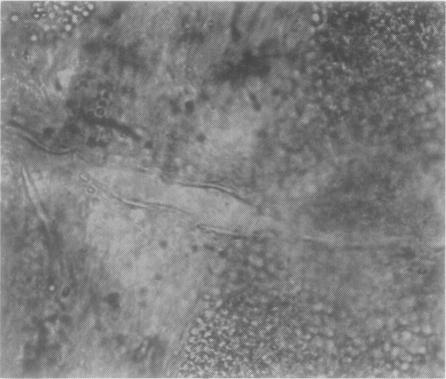

Fundus dystrophy with unusual features; a histological study.

Br J Ophthalmol. 1951 Dec;35(12):751-64. doi: 10.1136/bjo.35.12.751.